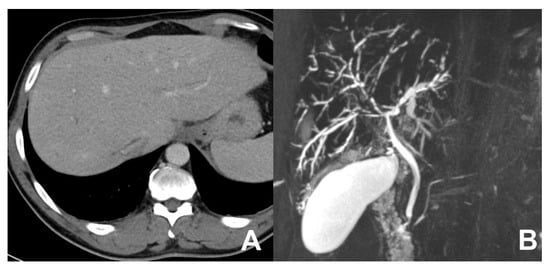

| MRCP 3D | OBLIQUE CORONAL | Biliary anatomy and calculi or stenosis | |||

| MRCP 3D | OBLIQUE CORONAL | -- | -- | use MIP and sub MIP for better detection of calculi | |

| MRCP 3D/2D | OBLIQUE CORONAL | Anatomy of wirsung duct | ||

| MRCP 3D/2D | OBLIQUE CORONAL | Relationship between the wirsung duct and the cystic lesion | ||

| MRCP 3D/2D | OBLIQUE CORONAL | Comprehensive evaluation of the wirsung duct and cystic lesions | ||